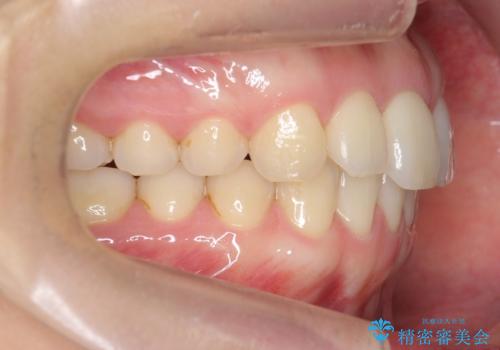

下の前歯が1本短い インビザラインと部分矯正の組み合わせ

- 前歯のガタつきと、下の前歯が一本短いことを主訴に来院。

インビザラインのマウスピースではめる装置で歯を引っ張り出すことは難しいと説明し、下の前歯だけワイヤー部分矯正を行ってからインビザライン矯正で仕上げをしました。

難しい部分を短期間ワイヤー矯正を行ってからのインビザラインは、全体治療が短くなるだけでなく、仕上がりもよくなるのでオススメです。